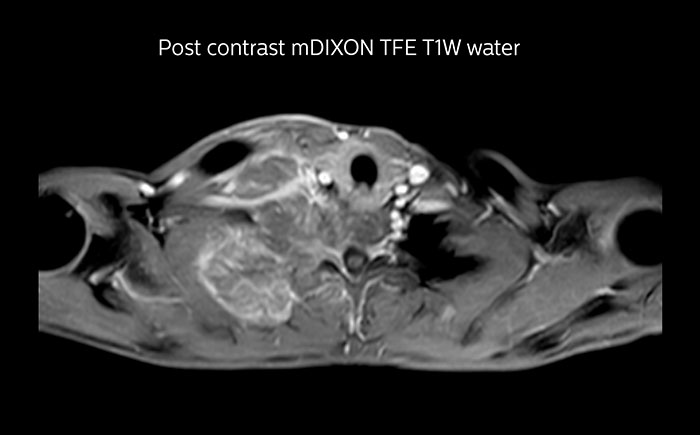

MRI of Pancoast tumor

Although the area between the neck and the top of the lung is one of the most difficult areas for MRI, Prodiva 1.5T images show good quality in this 56-year-old male with Pancoast tumor on the right. mDIXON TFE images shows excellent fat suppression in the neck area and the DWI shows almost no distortion.